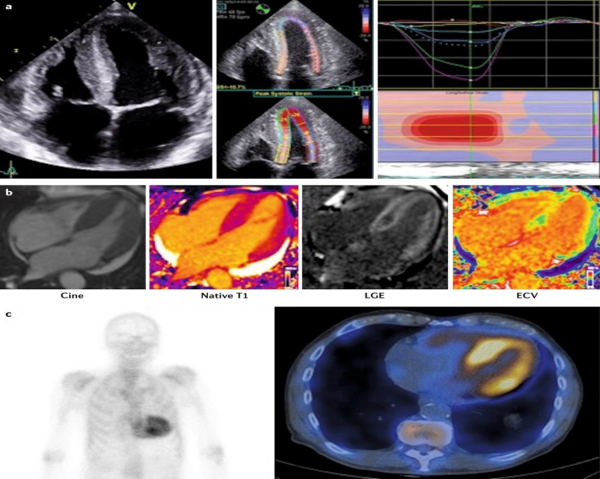

Si on avait réalisé une IRM cardiaque chez ce patient, quels signes auraient été évocateurs d’une amylose (Figure 12) ?

- Réhaussement tardif sous-endocardique ou transmural diffus

- Cinétique anormale du gadolinium (annulation du signal du myocarde avant celui du sang sur la séquence Ti scout)

- ECV ≥ 0,40 % (fortement favorable, mais non essentielle/diagnostique)

Figure 12 : Intérêt de l’imagerie multimodalité3